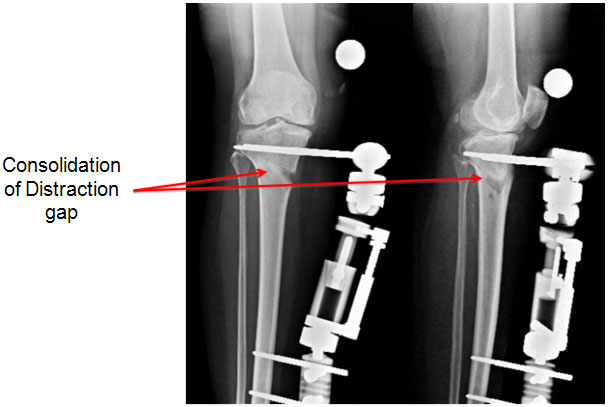

| 7 weeks |

| |